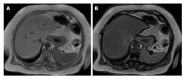

Nonalcoholic fatty liver disease (NAFLD) is one of the most common causes of chronic liver disease and is a major public health problem worldwide. It is a spectrum that includes simple steatosis, nonalcoholic steatohepatitis (NASH), fibrosis and cirrhosis. Recently, NAFLD prevalence in children and adolescents has increased too. The increasing prevalence has resulted in NASH-related chronic liver disease. Therefore, early diagnosis and treatment is quite important. Although liver biopsy is still the gold standard for diagnosis and staging of NAFLD, particularly for the diagnosis of NASH, imaging methods such as ultrasonography, computed tomography, magnetic resonance imaging with chemical shift imaging and especially magnetic resonance spectroscopy and elastography have been increasingly approved as noninvasive alternative methods. The aim of this review is to analyze the diagnostic accuracy and limitations of the imaging methods and recent developments in the diagnosis of NAFLD.